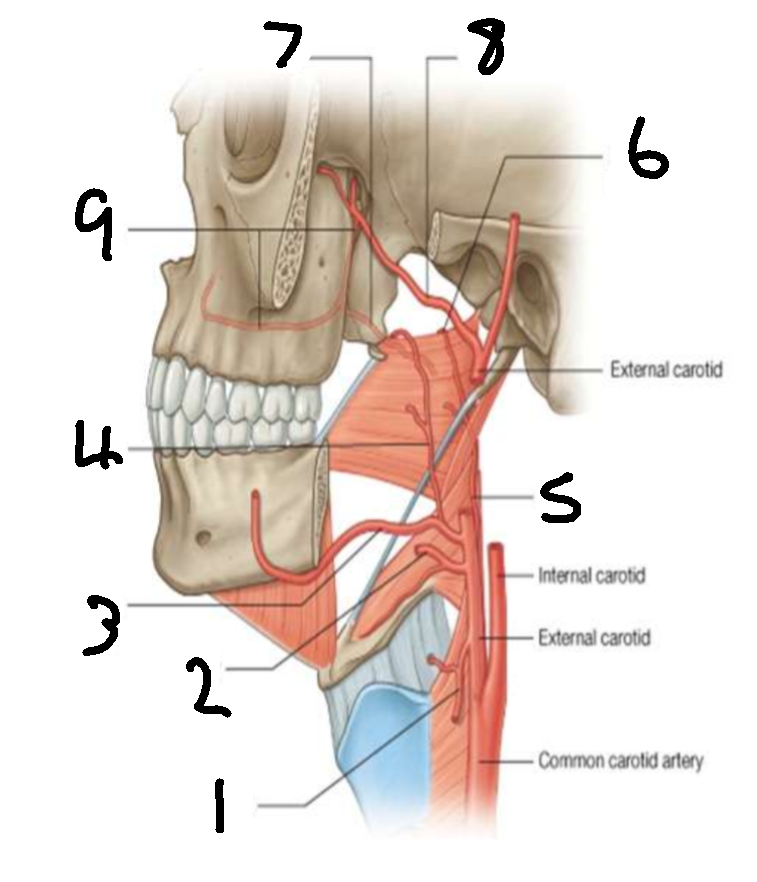

What is 1?

superior thyroid artery

What is 2?

lingual artery

What is 3?

facial artery

What is 4?

ascending palatine artery

What is 5?

ascending pharyngeal artery

What is 6?

palatine branch of pharyngeal artery

What is 7?

lesser palatine artery

What is 8?

maxillary artery

What is 9?

greater palatine artery